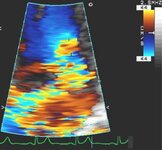

Apical 4-chamber view of 4+ (severe) mitral regurgitation and a large proximal isovelocity surface area

From the collection of Samir Kapadia and Mehdi H. Shishehbor

See this image in context in the following section/s: